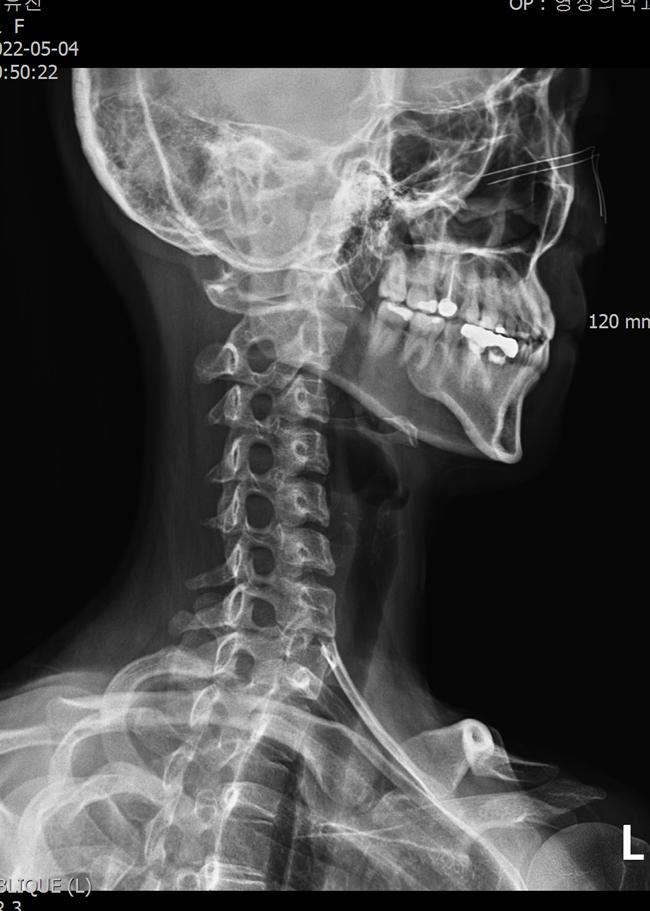

3) Cervical X-ray

The first imaging step is a neck X-ray to check alignment, disc height, and foraminal space.